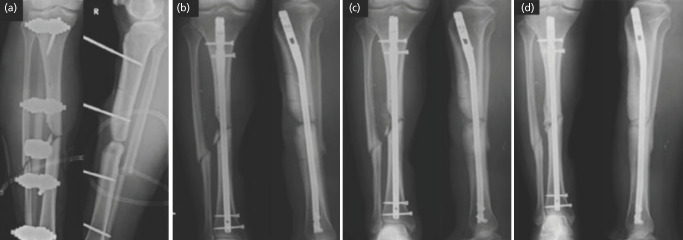

Materials and methods: We conducted a prospective randomised controlled trial at a single tertiary centre involving adult patients with long bone fractures that had undergone non-union and requiring bone grafting only. Autologous iliac crest bone graft was applied to the debrided non-union site, with additional fibrin glue applied for the intervention arm. Patients were followed-up with serial radiographs until clinical and radiographical union.

Results: Ten patients (3 male, 7 female), of mean age 41.7 (19 - 63) were recruited over five years, with one drop out. Eight out of nine fractures united after treatment. One patient underwent hypertrophic non-union requiring re-fixation and bone grafting. There was no difference in the time to union for patients in the fibrin glue group (19.5 weeks) versus the control group (18.75 weeks) (p=0.86). There were no complications sustained from usage of fibrin glue.

Conclusion: Fibrin glue appears to be a safe adjunct for treatment of non-union of long bone fractures across varying fracture sites by holding the bone graft in place despite not demonstrating a faster time to union.